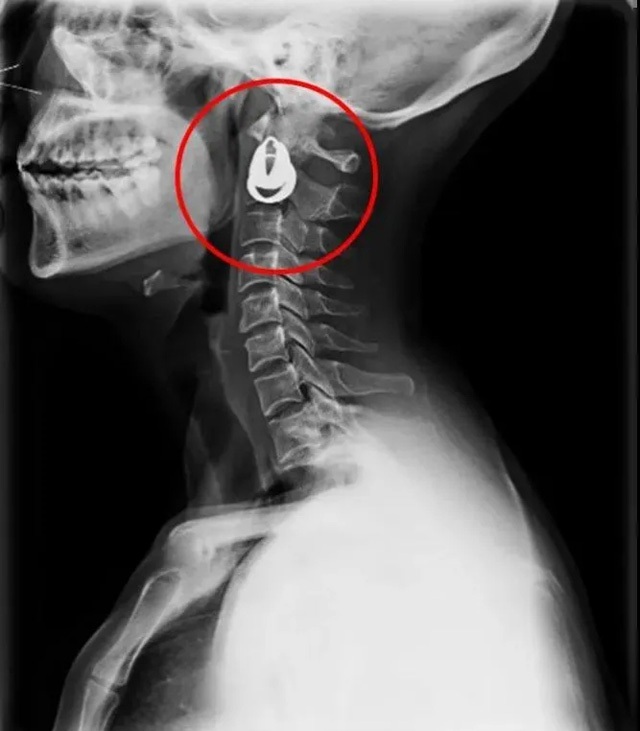

DR是一种比较常规的基础影像学检查方式,适用于人体各部位的健康普查及疾病检查等优势,在临床基础检查中备受医生和患者的青睐。DR体检车在健康体检中有着非常重要的地位,由通过电缆串接在一起的探测板、扫描控制器、系统控制及影像显示器等构成。对比CT检查而言,DR检查的价格更低,辐射剂量更小它可以让疾病预防,微细病变可更好显示诊断治疗提供科学的结果依据。很多外伤患者都要做DR检查,来判断是否骨折或其他的情况。体检过程中面对DR体检车做检查时候需要准备注意什么呢?很多时候大家都有这样的疑问,身上携带的物品是否会对图像造成遮挡或给机器带来干扰?检查前如何准备才不会影响检查准确性?